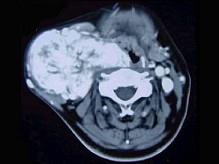

45岁,男性,颈部渐进性增大包块,CT增强扫描如图所示,请选择最可能诊断 ( )A、颈动脉体瘤B、甲状腺癌C、颈动脉夹层瘤D、神经鞘瘤...

问题 45岁,男性,颈部渐进性增大包块,CT增强扫描如图所示,请选择最可能诊断 ( )

选项 A、颈动脉体瘤 B、甲状腺癌 C、颈动脉夹层瘤 D、神经鞘瘤 E、颈部肿大淋巴结

答案 A